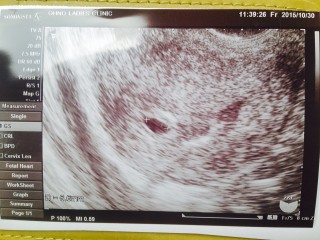

体外受精で初めて授かりました。 初めての陽性反応に、胎嚢確認。 先生も「よかったですね」と初めての笑顔を見せてくれました。 まだ6.6㎜で、心拍確認までは緊張しますが心穏やかに過ごしたいです。